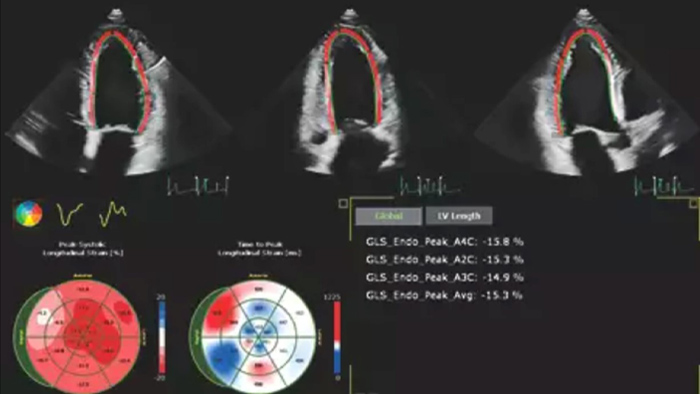

Heart failure is prevalent worldwide, and accurate assessment of heart function using echocardiography is essential.1,2 Incorporating strain and 3D assessment of the LV and RV has historically been challenging and required specialized skill sets.

Solution Philips IntelliSpace Cardiovascular multimodality image and information management solution offers a complete look at a patient’s cardiac history. The AI-enabled automation of Philips EPIQ CVx cardiovascular ultrasound system and Philips TOMTEC -ARENA quantification tools provides efficiency and reproducibility during echocardiography studies.

Philips solutions allow for advanced quantification and analysis, with access to information anywhere, anytime across the enterprise. AI-enabled, automated tools for visualization, analysis and streamlined reporting offer robust, reproducible results to help make the effective management of heart failure a reality.

Echo is often the first cardiac imaging test that’s performed for patients with suspected heart failure. An echocardiogram gives us a wealth of information on cardiac structure and function using both 2D and 3D tools. Echocardiography can help us understand the etiology of heart failure in many situations. I routinely use information derived from both 2D and 3D analysis and strain to better understand my patients. AutoStrain, Dynamic HeartModel and Auto RV are invaluable tools that are used both in the diagnosis and surveillance of patients with heart failure.”

Robust and reproducible imaging tools are important to diagnose and monitor disease progression in heart failure. Current guidelines support the use of advanced echocardiography tools such as longitudinal strain and 3D assessment of LV and RV volumes and function.

Automation for robust, proven reproducible cardiac quantification in both 2D and 3D.

Quantification through Dynamic HeartModel.